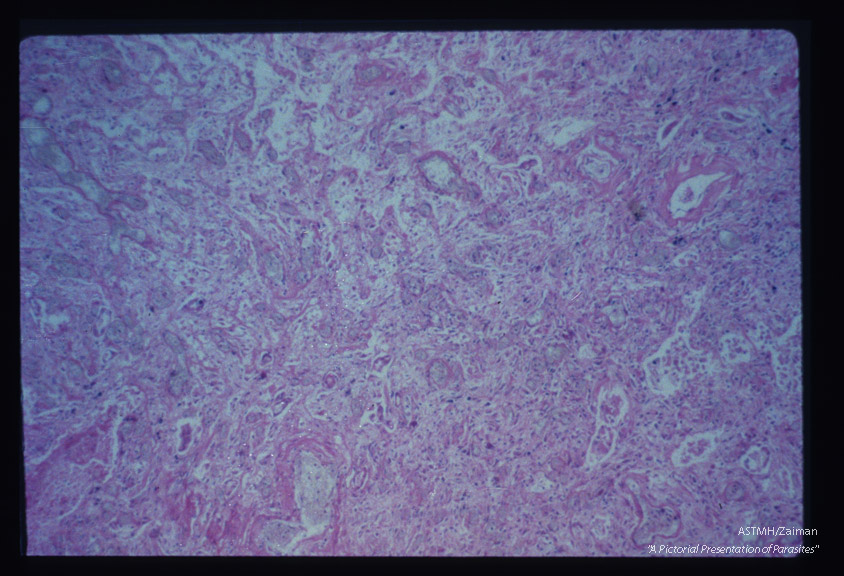

Wall of pulmonary abscess.

Entamoeba histolytica

Description: Wall of pulmonary abscess.